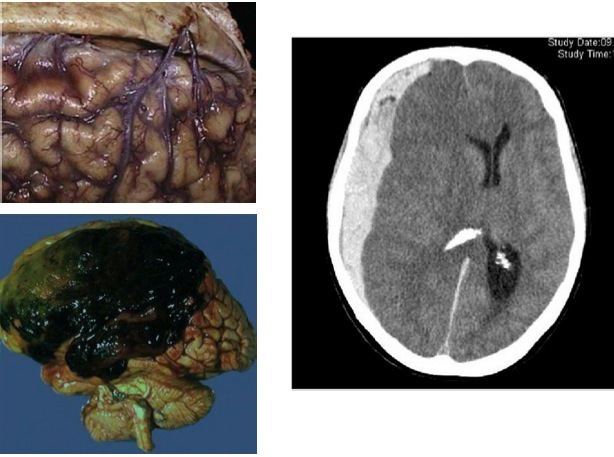

Diffuse Axonal Injury (DAI)

Vascular malformations

AVMs

– Greatest potential for hemorrhage

– High flow channels without arterial structure -> high calibre vessels in cortex where it should small calibre

– Rx: excision, endovascular occlusion, spray embolic agents